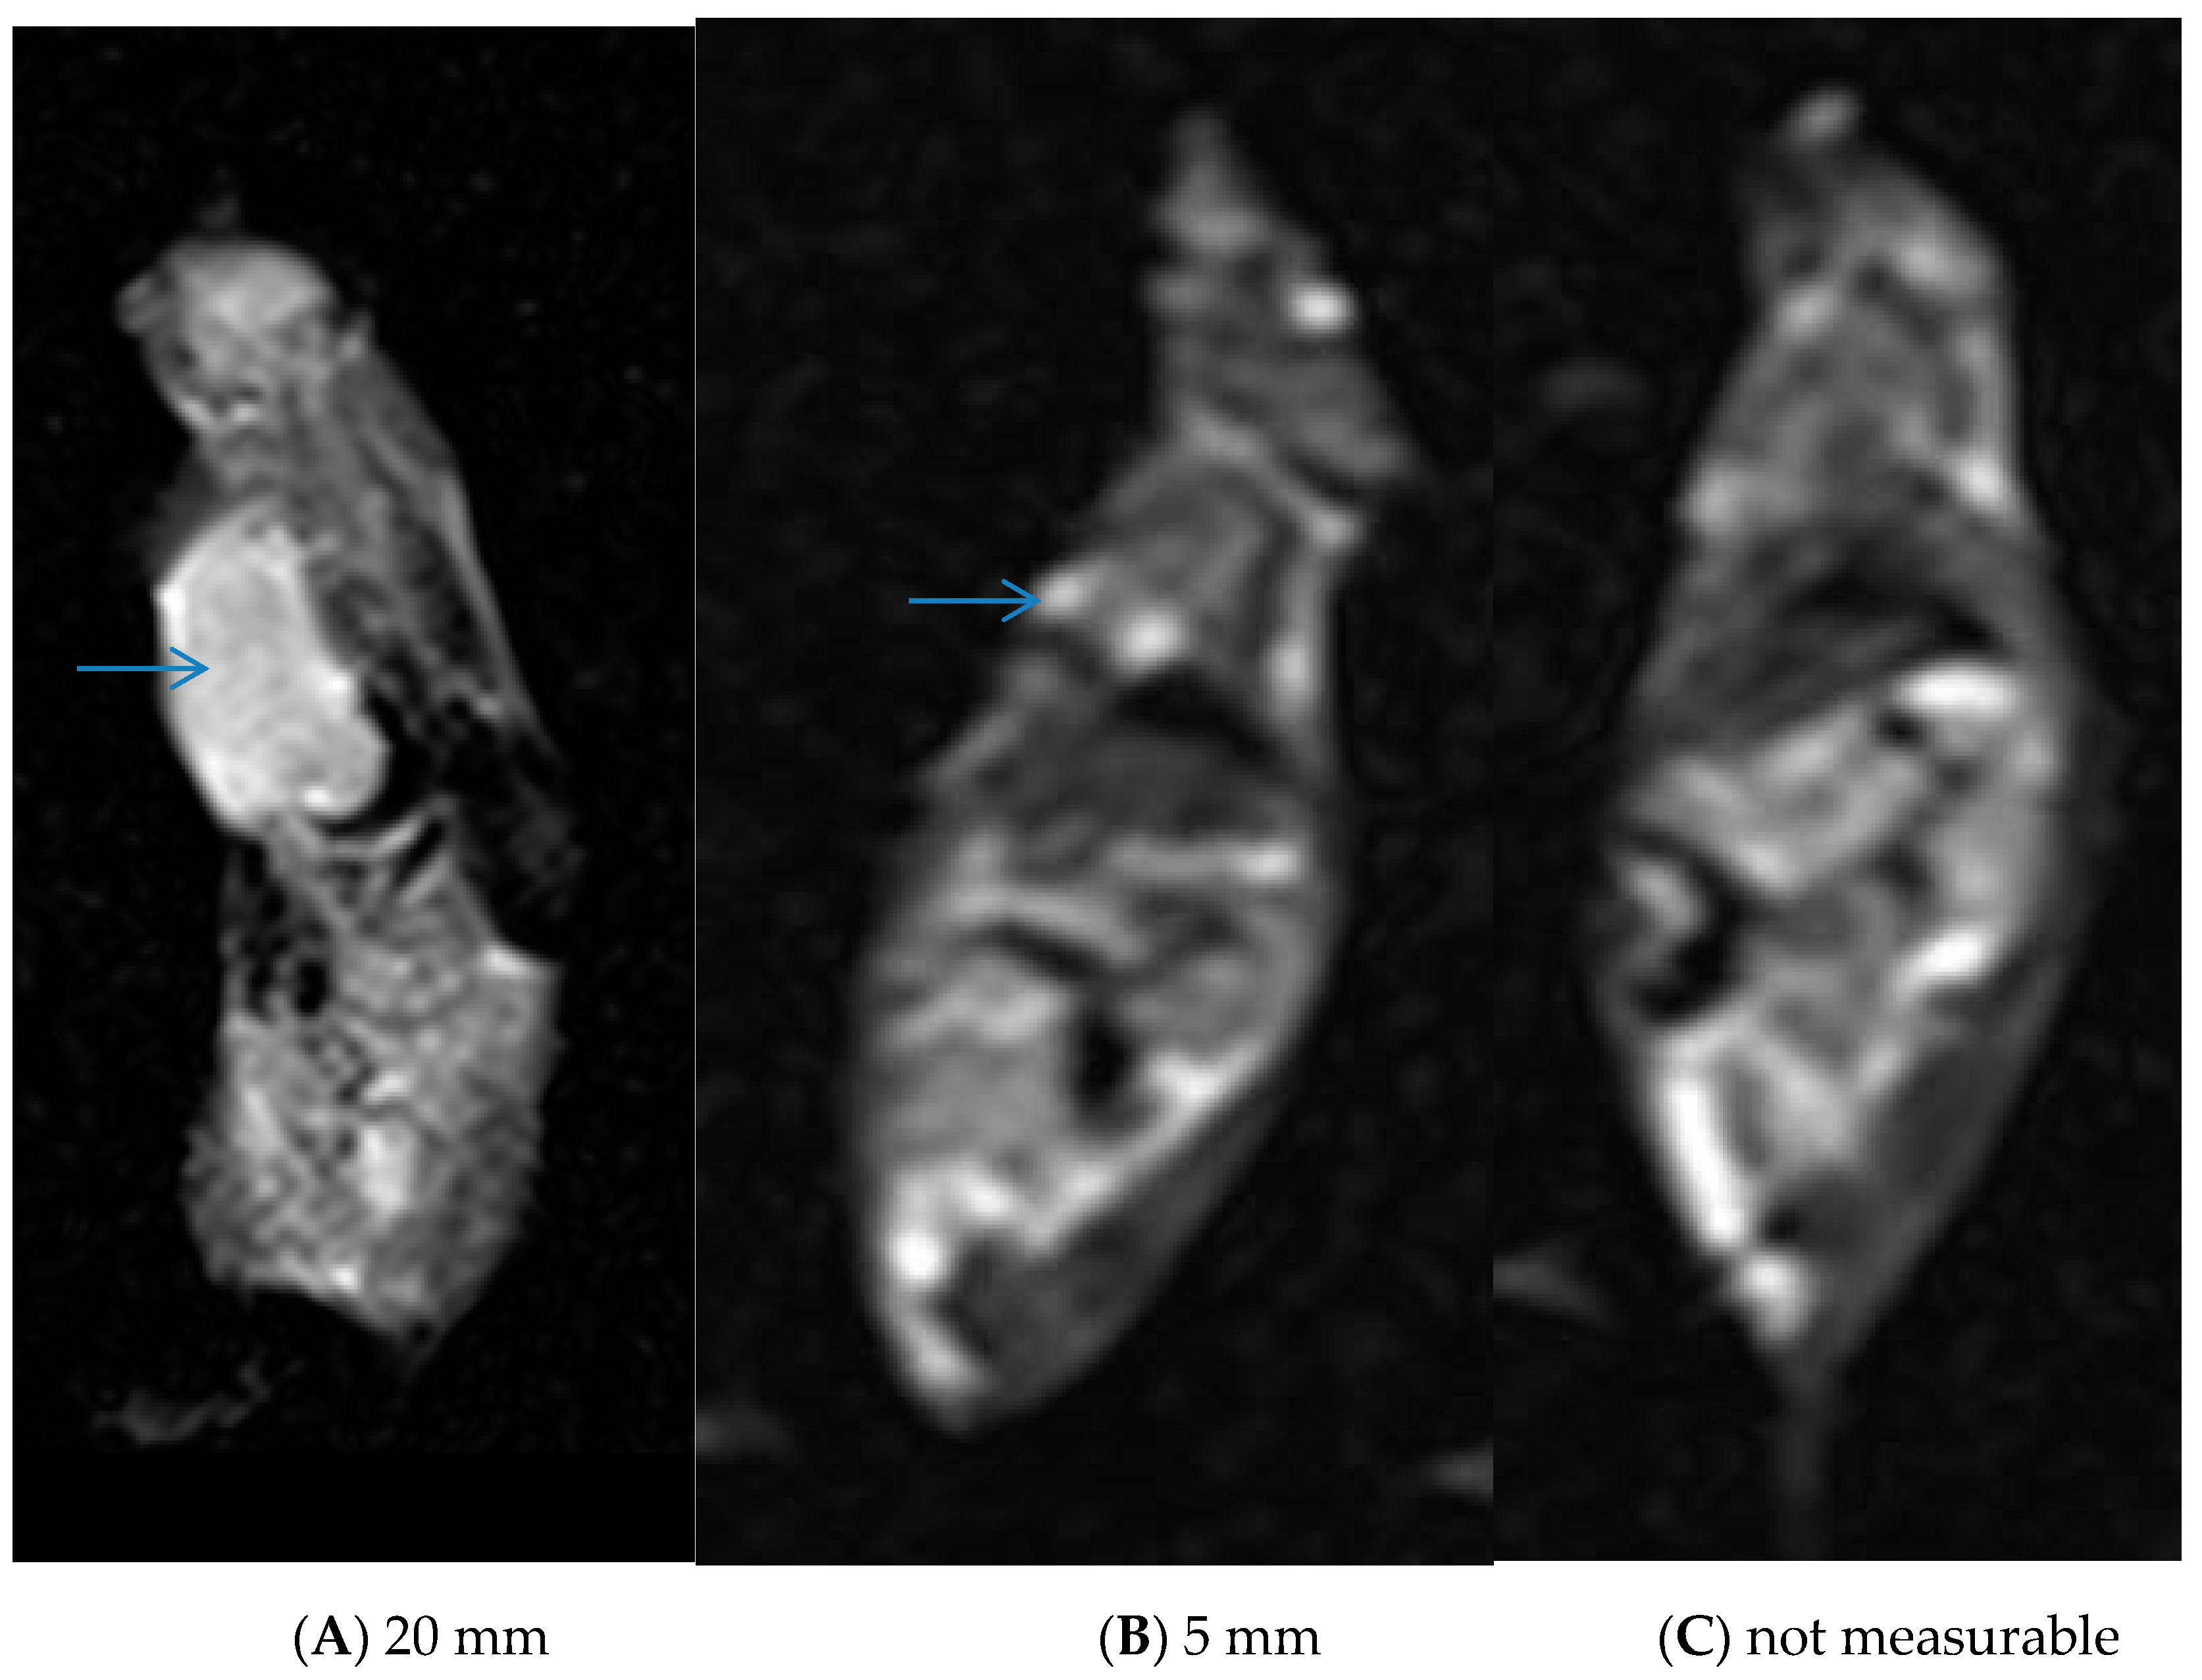

3.5. In Vivo Experiments and MRI Analysis